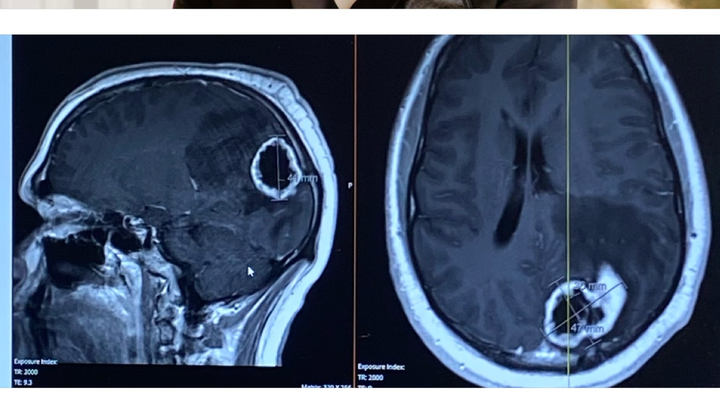

Hello! My name is Avery and I am a long-time family friend of the Koenigs. Well, actually I’m more like their adopted daughter. Eli is literally my brother from another mother. For those of you who don’t know Eli, he is only 26 and one of the kindest souls I know. Unfortunately, Elijah Koenig has been recently diagnosed with a walnut-sized brain tumor. We are unsure if it is benign or malignant, but the MRI reading suggested malignancy. He is scheduled to get his tumor, Fred (as Eli has named it), removed on Monday 8/18/25. As one can imagine, brain surgery is NOT cheap. Not only the surgery, but the hospitalization and rehabilitation afterwards. I’m hoping this GoFundMe will help relieve some financial stress that this type of situation comes with. We appreciate any amount you can give, thank you!